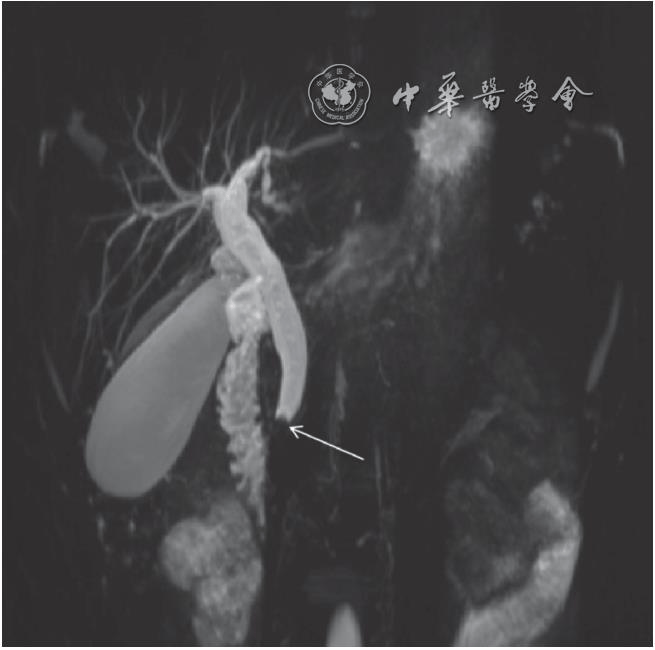

其无需插管或注射对比剂,即可无创显示胆管和胰管的全程结构,对胆总管下端结石胰管狭窄或先天性变异如胰腺分裂症的诊断准确率超过95%MRCP与MRI联合应用时,可同步评估胰腺实质病变与胰胆管受累情况,例如在诊断胰腺癌时,既能发现胰头占位,又能明确胆总管末端是否受侵导致梗阻联合检查的必要性。

MRCP是指磁共振胰胆管水成像,主要用于检查肝胆管系统疾病以及胰腺疾病,是一种无创性磁共振检查磁共振水成像技术代表着先进技术手段和具有无创性特点,已为国内外医师所关注并广泛应用于临床在MRCP之前展示胰胆管系统形态和病理改变,应用内镜逆行胰胆管造影即ERCP,需要经消化道插管注入造影剂,需要麻醉。